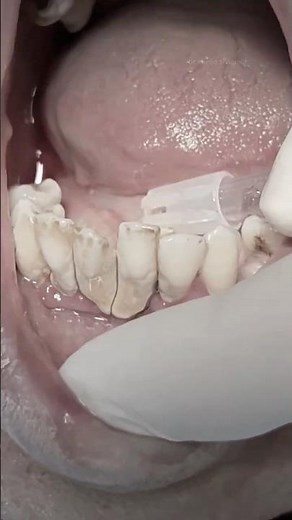

Calculus Bridge Removal

0:18

Effective Teeth Cleaning Techniques for Calculus Removal

TikTok

5starsmiles

2022年11月3日

BIG CHUNK OF CALCULUS REMOVAL

YouTube

Dr.Massi Dental Clinic

已浏览 1.5万 次

10 个月之前

0:33

Heavy calculus scaling and extraction of mobile teeth to replace with bridge soon #dentist #shorts

Dr Morad Shaglouf

已浏览 4043.2万 次

2025年1月29日